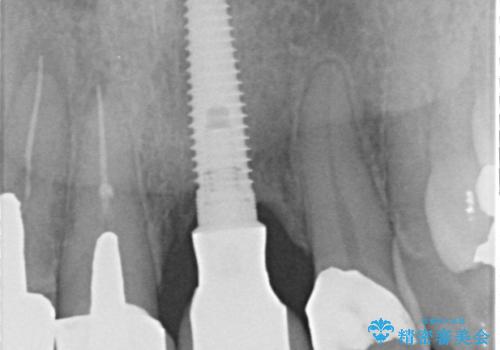

左側の前歯には他院で埋入されたポジションの悪いインプラント補綴により歯冠長の長いクラウンが装着されており、感染による排膿も認められこのまま審美性を改善するのは難しい状態です。

感染したインプラントについて

感染したインプラントからは排膿が間欠的に認められ、掻爬・除去が検討されうるような状況でした。

より審美的な改善を強く求められたため、インプラントを除去し可及的に欠損部顎堤を増大したのちブリッジによる審美改善を行いました。